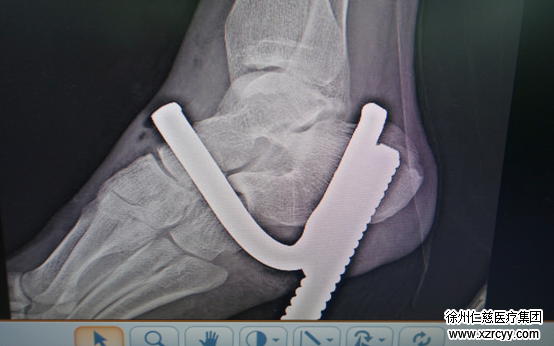

接诊后,急诊科的医护人员立即对丁某进行了止血、清创、包扎处置和检查。经过体查,医生发现钢筋上的钩子从伤者的右脚足底斜行贯通至足背。钢筋距离足背的长度大概6到7公分。

“情况还是比较凶险的。钢筋与足底的重要血管、神经距离很近,加之钢筋上带有大量的细菌和有害物质,伤口内污染严重,必须紧急手术。”11时许,待反复消毒后,我院手外三病区副主任刘衍松为丁某实施了异物取出术。刘主任一边对创口内肌肉及软组织进行消毒处理,一边一点一点把插在丁某足底的钢筋拔出,又顺着伤者脚部的“窟窿”进行引流,以免化脓。